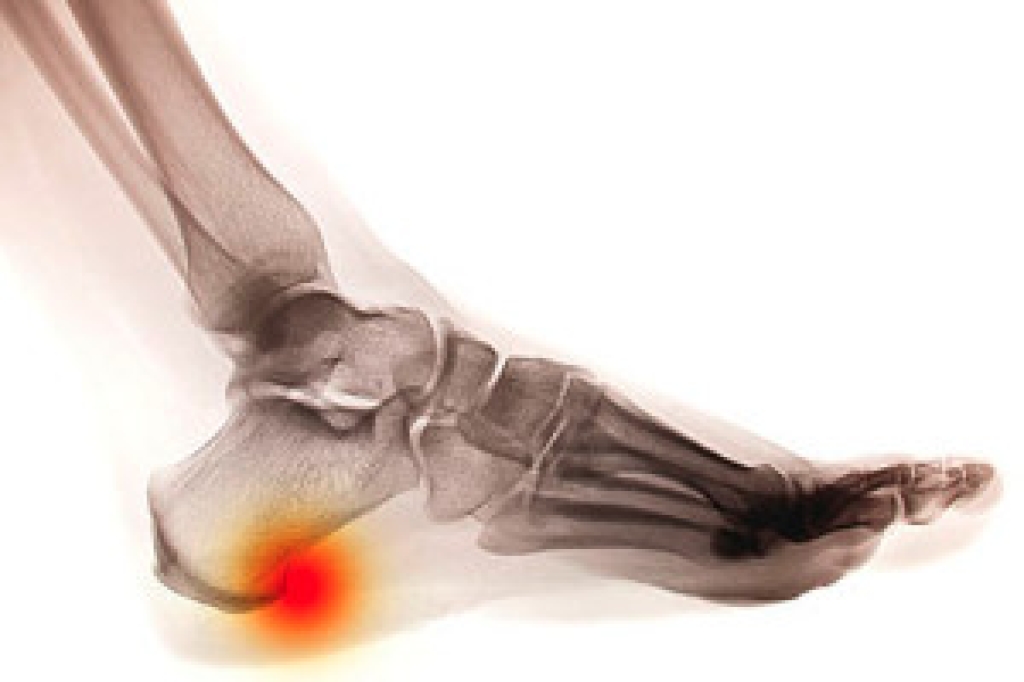

Peripheral artery disease (PAD) is a circulatory disease that narrows arteries and restricts blood flow in the extremities. This can cause cramping in the legs when exercising, which usually subsides when you stop. PAD can also cause pain, numbness, swelling, and discoloration in the feet, and can be a prelude to more dangerous complications. One of the tests a podiatrist may use to test the blood flow through arteries and veins is a duplex ultrasound. There are two components to a duplex ultrasound. The first is traditional ultrasound which creates an image by bouncing sound waves off of blood vessels. The second is doppler ultrasound which measures sound waves reflected off of flowing blood to visualize its direction and speed. Duplex ultrasounds are non-invasive. The patient remains still as the podiatrist hovers a wand (transducer) over the area to be tested which sends out sound waves. These sound waves are then reflected back and translated into images. To learn more about PAD and various ways to test for it, please make an appointment with your local podiatrist.

Vascular testing checks for how well blood circulation is in the veins and arteries. This is most often done to determine and treat a patient for peripheral artery disease (PAD), stroke, and aneurysms. Podiatrists utilize vascular testing when a patient has symptoms of PAD or if they believe they might. If a patient has diabetes, a podiatrist may determine a vascular test to be prudent to check for poor blood circulation.